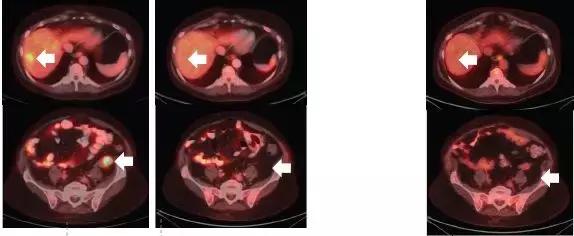

昨天关于第二代TRK靶向药物的论文刚刚发表,最初的两位耐药患者尝试新药后,肿瘤再次快速缩小。比如下面这位,用药一个月后,耐药的肿瘤就再次几乎消失!

耐药后 使用2代药一个月后